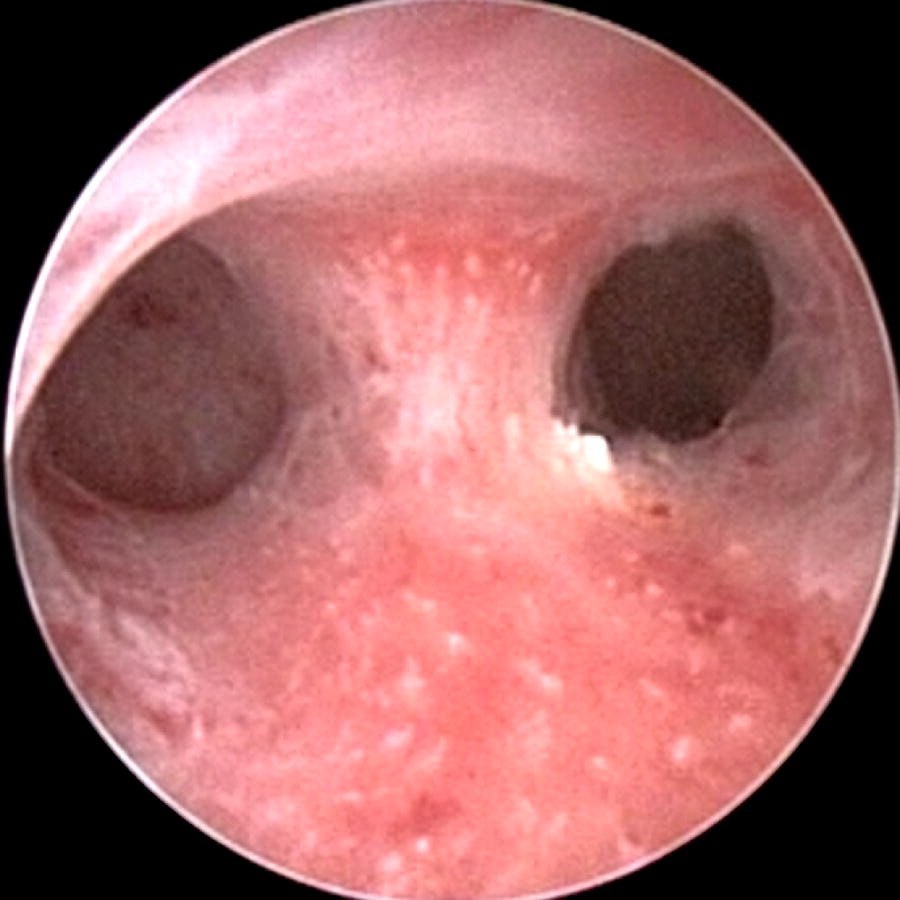

A septate uterus is a deformity of the uterus, which happens during fetal development before birth. A membrane called the septum divides the inner portion of uterus, at its middle. This dividing septum is a fibrous and muscular band of tissue that can be thick or thin.

A septate uterus can be treated with a surgery called a metroplasty. The procedure is now carried out with a hysteroscopy. The hysteroscopic procedure allows for treatment to be done within the uterus without the need for an outer abdominal incision.

During a hysteroscopic metroplasty, a lighted instrument is inserted into the vagina, through the cervix and into the uterus. Another instrument is also inserted to cut away and remove the septum.